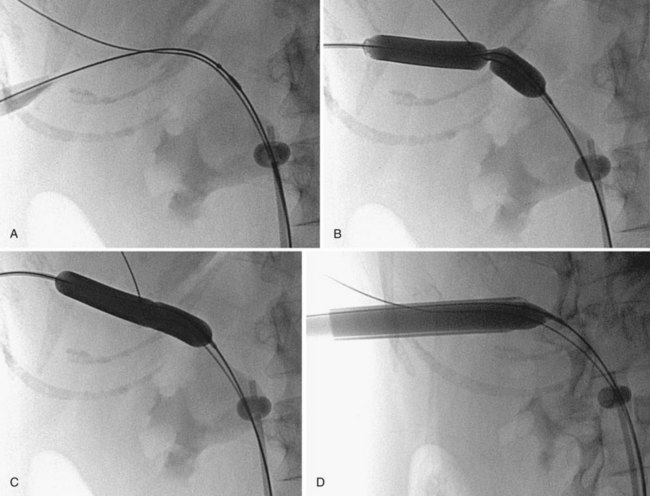

Balloon dilators (Fig. 47–25) were developed to obviate the repetitive dilations of the rigid metal and semirigid plastic dilation systems, which are both time consuming and potentially dangerous. This is the most common dilation method for percutaneous renal surgery today (Benway and Nakada, 2008). The appropriate working sheath is back-loaded onto the balloon dilation catheter, which is passed over the working wire until the radiopaque marker is at the intended depth of dilation (Fig. 47–26). The dilating balloon is inflated with a pressure syringe. A “waist” appears at the site(s) of greatest resistance, usually the abdominal wall fascia and the renal capsule (Fig. 47–26B). Once the balloon is fully expanded (Fig. 47–26C), the working sheath is passed over the balloon (Fig. 47–26D) (Fig. 47–27 on the Expert Consult website

). The balloon catheter has a “shoulder,” which is the portion between the end of the balloon and the point at which the maximal diameter is achieved. The sheath should not be passed beyond the maximal diameter of the balloon because this can cause significant injury. Balloon dilators, which are expensive one-time use devices, are less effective than rigid metal and semirigid plastic dilation systems in densely scarred tissue but are more effective when the kidney is hypermobile (Kumar and Keeley, 2008). Most (Heggagi et al, 1991; Davidoff and Bellman, 1997; Safak et al, 2003; Kukreja et al, 2004), but not all (Gonen et al, 2008a), studies have suggested that hemorrhage and transfusion rates are less with the balloon dilators compared with rigid metal and semirigid plastic dilators.

Figure 47–26 Balloon dilation of tract and placement of working sheath. A, Balloon catheter is inserted over wire, with distal radiopaque marker is at the intended depth of dilation. B, “Waist” appears as balloon is inflated. C, Balloon is fully expanded. D, Sheath is passed over balloon, taking care not to advance it beyond the point of maximal diameter of the balloon.